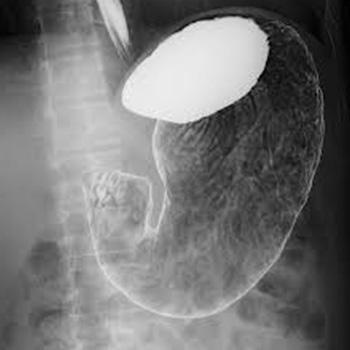

医療の分野では、放射線を使用した検査として、レントゲン検査・胃バリウム検査・CT検査・マンモグラフィ検査などがあります。